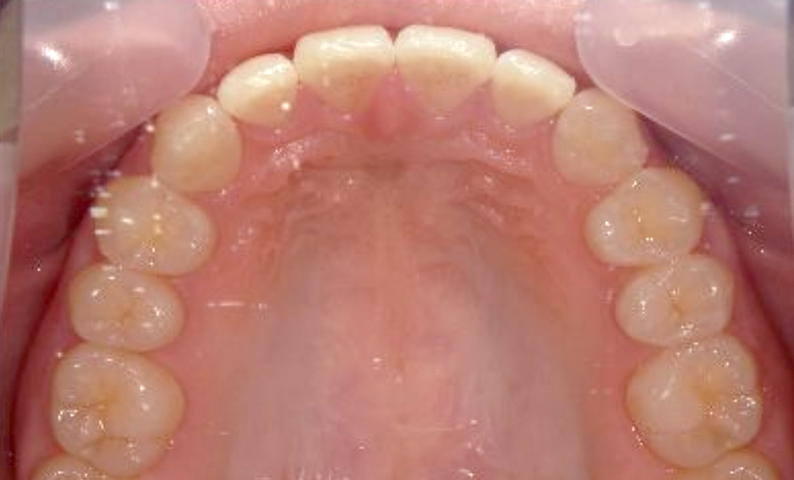

| 治療前 | 治療後 |

|---|---|

|